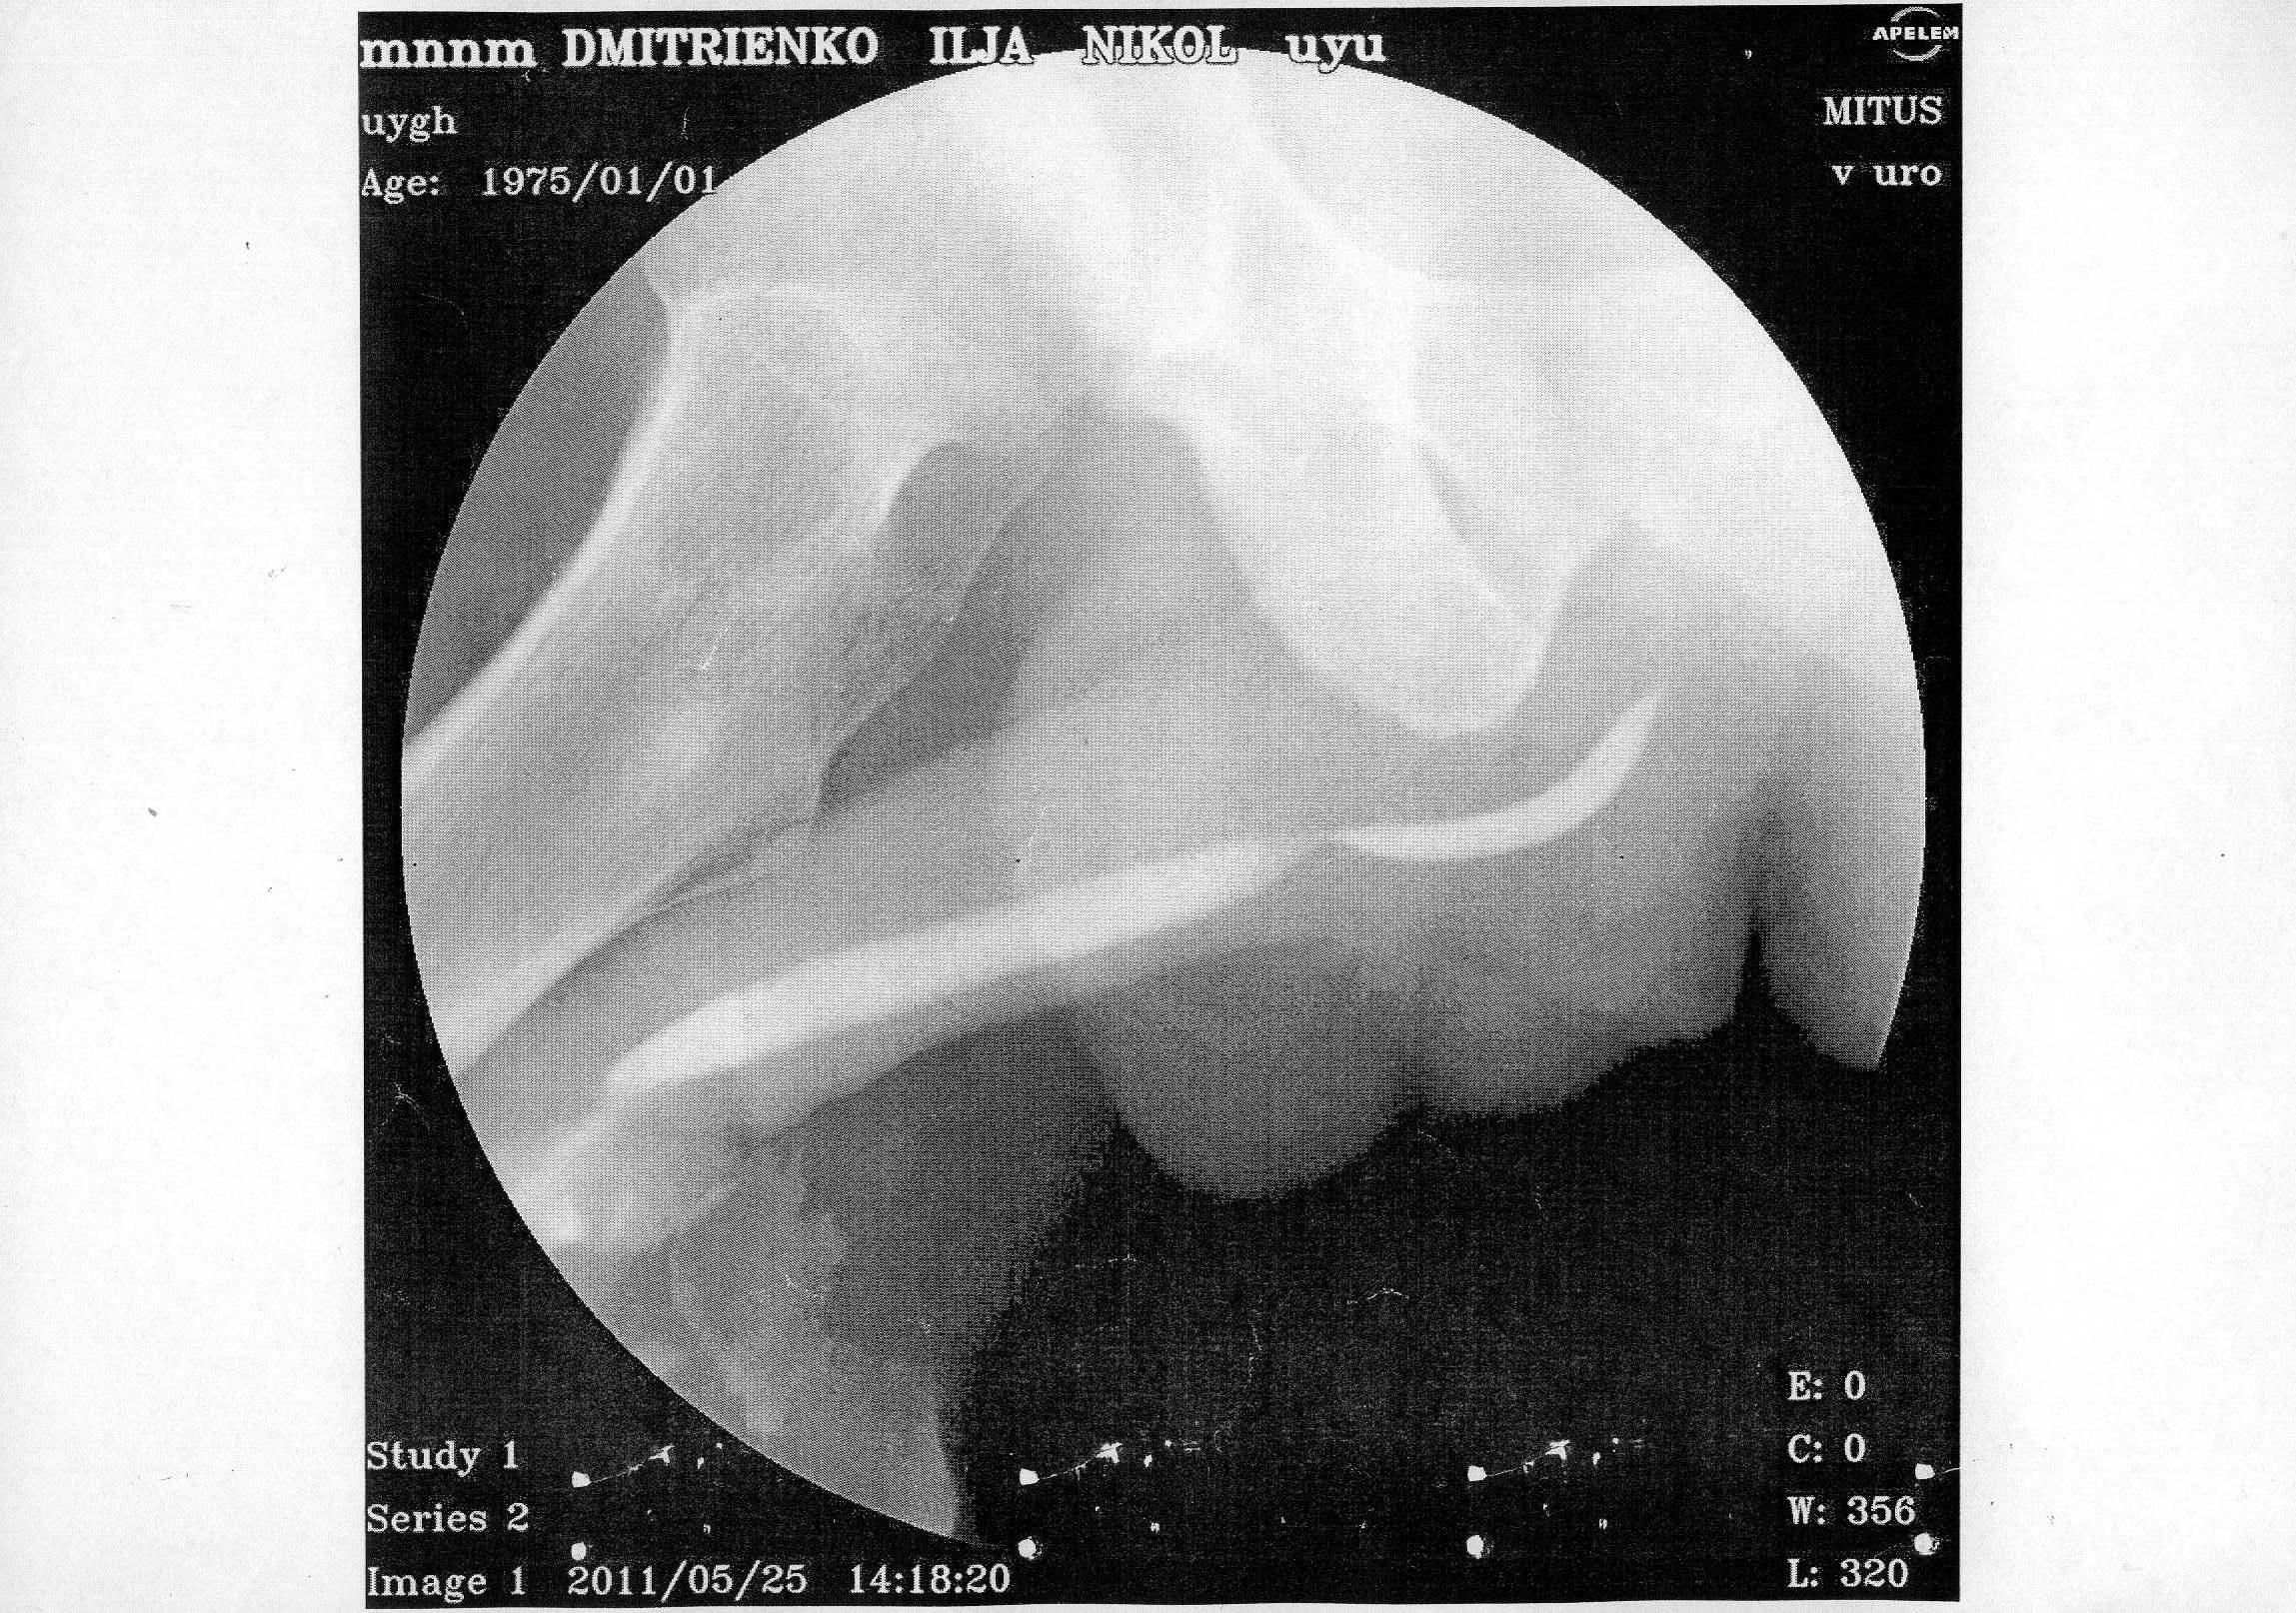

В начале 2011 года, в январе попал в , г. Алматы (был в командировке в Кзахстане)чеиспусканием, после проведенной уретроскопии, началось обострение, продержали в больнице неделю, вводили в/в антибиотики, была проведена инфузионно-детоксикационная терапия, физиолечение, делали восходящую и нисходящую уретроцистографии - б/о.

По приезду на Украину, боли не проходили в задней части уретры, было учащенное мочеиспускание, сдавал у местных урологов рахзличные анализы ПЦР на ЗППП - отрицательно, ОАМ, ОАК, различные посевы - все в пределах нормы. В конце марта сделал уже в г. Киева - КТ - на ней показало сужение простатической части уретры, было предложено бужирование, я отказался и поехал в Ростов, к профессору Когану, там провели исследования и сказали, что пока ничего не видят. Боли остаются, после полового акта боль усиливается, и учащается мочеиспускание. Не знаю, может быть болит семенной бугорок, могли задеть при уретроскопии, после которой и начались такие проблемы.